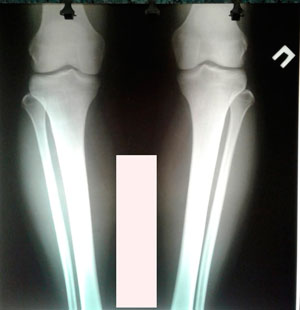

Исходник - 27 лет. Россия. Адыгея. Майкоп.

Дата операции - 11.10.2019.

IMG_6307-10-10-19-04-23.JPG

IMG_6301-10-10-19-04-23.JPG